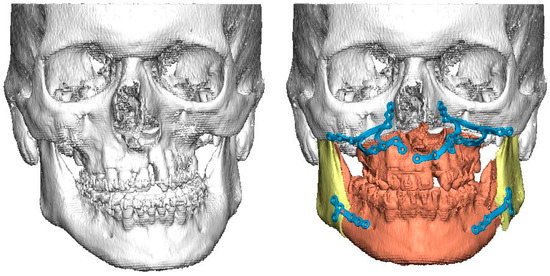

Medical charts from hospitals’ archives and databases were used for data collection. All patients had cone-beam computed tomography (CBCT) or computed tomography (CT) with a slice thickness of 1 mm or less and 0° gantry tilt taken for 3D planning purposes. The radiological anatomy of bony orbits was analyzed retrospectively from CT or CBCT imaging data that had been used in the virtual planning of orthognathic surgery and for CAD/CAM production of patient-specific surgical drill and cutting guides, as well as individualized osteosynthesis (Figure 1)

Figure 1.

On the left is a preoperative surface model of a patient with UCLP and severe midline asymmetry. On the right is the planned correction of bony asymmetry with CAD/CAM-generated patient-specific osteosynthesis for simultaneous Le Fort I osteotomy and bilateral sagittal split osteotomies.